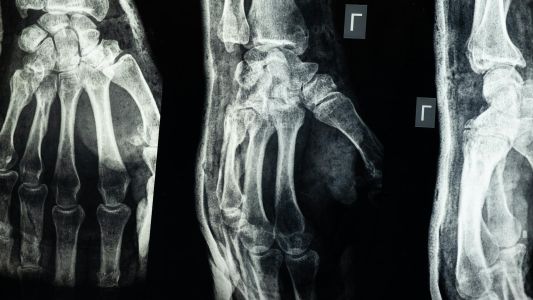

Multislajsni CT skener zglobova pruža detaljan prikaz kostiju i mekih struktura radi boljeg uvida u promene. Raduje pri bolu, sumnji na prelome ili praćenju hroničnih tegoba.